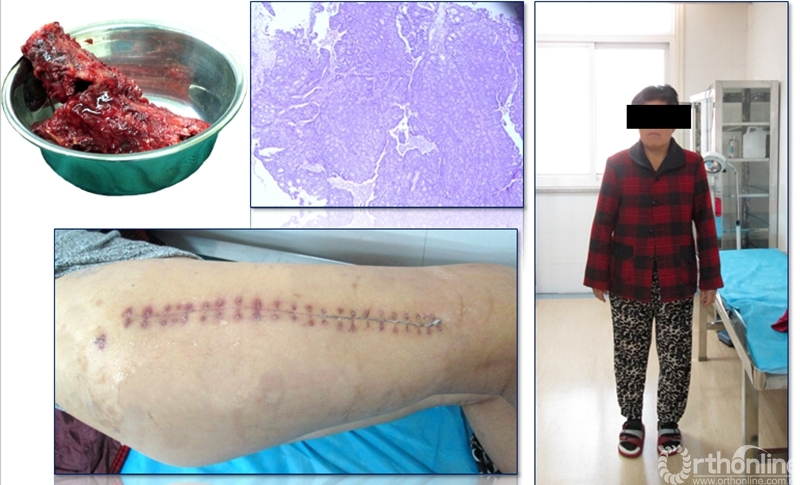

患者女性,68岁,乳腺癌病史,右股骨中段病理性骨折,股骨长段溶骨性破坏,并有跳跃病灶。病变的长度为16cm,病灶近端在小转移水平,因为近端髓腔柄较短,故选择A区骨干假体。经病理诊断为转移性腺癌,术后2周患者拆线后即可离床活动。

术后资料